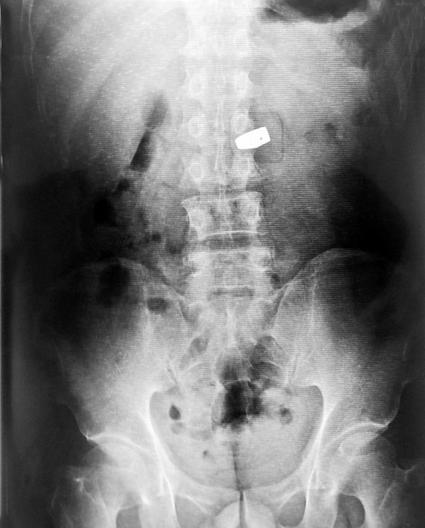

一名中國女游客秦某,在泰國曼谷珠寶展上趁人不備,把一顆價值200萬人民幣的 6克拉鉆石囫圇吞下。警方通過X光,找到位于其大腸中的鉆石,并讓醫生使用腸鏡等器械,將鉆石從該女子的腸中取出。人贓并獲時,女子竟然用日語對警察道歉 說“おわび申し上げます”(我對此非常抱歉)。

事后,警察在檢查護照時發現,該女子確系中國人。但是,值得注意的是,失竊的珠寶商也被一同抓了起來,因為涉嫌高價販賣假鉆——據悉,真鉆在X光下是無法被發現的。